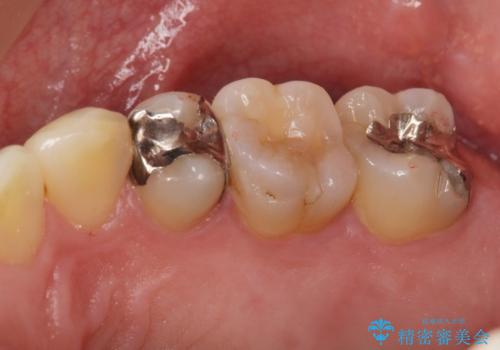

転んで前歯が折れた 色合いの難しい歯のセラミック修復

テトラサイクリン歯といって縞模様の強い歯の色調再現を行いました。

- 16.5万円(内訳:仮歯1万円、ジルコニアクラウン(スペシャル)14万円)費用は治療当時の料金となります